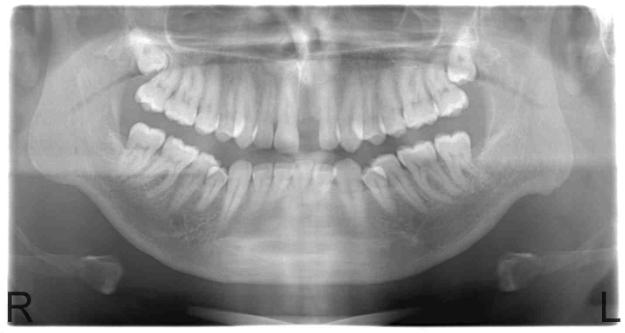

When 2009 rolled around, my health, yet again started to deteriorate, which considering all that I had already been through, was extremely depressing. I went back to the dentist that did the surgeries on me, he x-rayed my jaw and told me both sites had healed really well. This was my x-ray. You can see a little 'scarring' of the bone above where the teeth would have been, but you definitely can't seeany holes in the bone.